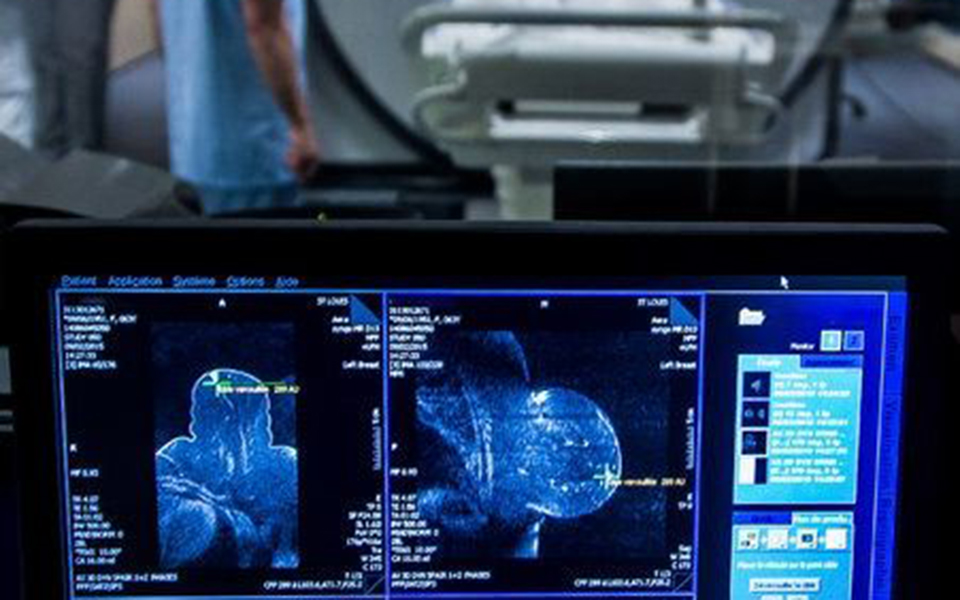

Μια νέα μελέτη, που εκπονήθηκε στην Ολλανδία και δημοσιεύθηκε στην επιθεώρηση New England Journal of Medicine, αποδεικνύει ότι η συμπληρωματική μαγνητική τομογραφία των μαστών είναι πολύ πιο αποτελεσματική στη διάγνωση του καρκίνου από ό,τι μόνο η μαστογραφία. Στην επιστημονική έρευνα συμμετείχαν 40.000 γυναίκες με εξαιρετικά πυκνούς μαστούς. Διαπιστώθηκε ότι σε αυτές που υποβλήθηκαν και σε μαστογραφία και στη συνέχεια σε μαγνητική τομογραφία, ανιχνεύθηκαν περισσότεροι καρκινικοί όγκοι συγκριτικά με όσες υποβλήθηκαν μόνο σε μαστογραφία. Επίσης, οι Ολλανδοί επιστήμονες διαπίστωσαν ότι οι γυναίκες που υποβλήθηκαν σε μαγνητική τομογραφία διέτρεχαν λιγότερες πιθανότητες να εντοπίσουν κάποιον ψηλαφητό καρκινικό όγκο κατά το διάστημα ανάμεσα στις δύο τακτικές εξετάσεις τους. Οταν οι όγκοι μπορούν να ψηλαφηθούν, είναι μεγαλύτεροι, γεγονός που σημαίνει ότι ο καρκίνος έχει προχωρήσει.

Περίπου οι μισές γυναίκες άνω των 40 ετών διαθέτουν πυκνούς μαστούς, έχουν δηλαδή περισσότερο συνδετικό και ινώδη ιστό και σχετικά λιγότερο λίπος. Οι γυναίκες με πυκνούς μαστούς διατρέχουν αυξημένο κίνδυνο να εμφανίσουν καρκίνο συγκριτικά με όσες διαθέτουν λιπώδεις μαστούς. Παρά τη μεγάλη σημασία των αποτελεσμάτων της ολλανδικής μελέτης, παραμένει αβέβαιο κατά πόσον η προσθήκη μαγνητικής τομογραφίας στην τακτική μαστογραφία μειώνει τα ποσοστά θανάτου από τη συγκεκριμένη μορφή καρκίνου. Επίσης, υπάρχει κάτι το αρνητικό στις διαγνωστικές τομογραφικές εξετάσεις, καθώς συχνά δίνουν ψευδώς θετικά αποτελέσματα, που καταλήγουν σε περιττές βιοψίες, ενώ ταυτόχρονα παρέχουν τη δυνατότητα ανίχνευσης ορισμένων καρκινικών όγκων σε εξαιρετικά πρώιμο στάδιο, οι οποίοι πιθανόν να μην απειλήσουν ποτέ την επιβίωση της γυναίκας, όπως επισημαίνει η Κάρλα φαν Γκιλς, καθηγήτρια κλινικής επιδημιολογίας στο πανεπιστημιακό ιατρικό κέντρο της Ουτρέχτης, η οποία και υπογράφει την έρευνα. Ωστόσο, η δρ Φαν Γκιλς επισημαίνει ότι η σαφής αδυναμία στη διάγνωση ενδιάμεσων καρκίνων, δηλαδή αυτών που διαγιγνώσκονται έπειτα από αρνητική μαστογραφία, υποδεικνύει ότι η προσθήκη μαγνητικής τομογραφίας ίσως να είναι ένα σωτήριο «εργαλείο» για τις γυναίκες με πυκνούς μαστούς.